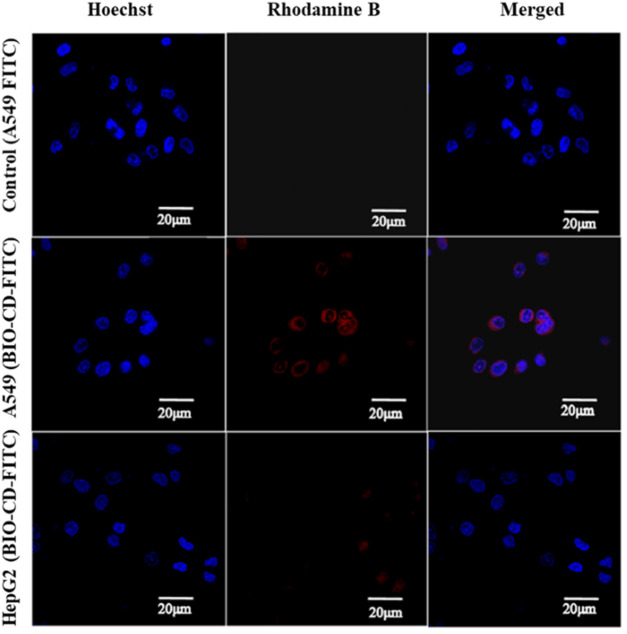

Selective Cellular Uptake

Through cell uptake studies on Hela, A549, and LO2 cells, the selective targeting properties of BIO-CD were determined. Cells were inoculated into culture dishes (20 mm, PS, 5,000 cells/dish), and then incubated overnight. The BIO-CD loaded with Rhodamine B was incubated with cells for 6 h. As Rhodamine B yields red fluorescence, it could be used to examine the intracellular localization of BIO-CD particles. The nucleus was identified by Hoechst staining, which yields blue fluorescence. Confocal laser scanning microscopy (CLSM, Eclipse Ti, Nikon) was used to record the intracellular localization of the samples. All cells were carried out in triplicate.

Targeted Drug Delivery to Tumor Cell Models

The prerequisite for drug delivery is biocompatibility. In the cytotoxic test under different incubation times, the BIO-CD exhibited high biocompatibility (Table 3). Besides the established biodegradability of previous study, it also had biocompatibility of practical drug delivery applications. Since CBD enhanced cellular uptake by the biotin receptor mediated cellular uptake, the cytotoxicity of AD-CBD/BIO-CD was enhanced, as shown in the following experiments.

Therefore, the feasibility of targeted drug delivery of using BIO-CD was evaluated in our study. The model drug Rhodamine B was used to demonstrate that the BIO-CD polymer delivered the drug selectively to the biotin receptor overexpressed cancer cells. The two cell lines of HeLa cervical cancer and A549 human lung cancer have different biotin receptor expression levels on the cell membranes, thence, they are used as cell models. From the confocal image, the copolymer loaded with Rhodamine B was combined with HeLa cells selectively. But the fluorescence of the cell surface of A549 was negligible, indicating the biotin receptor targeting ability of BIO-CD (Figure 12).